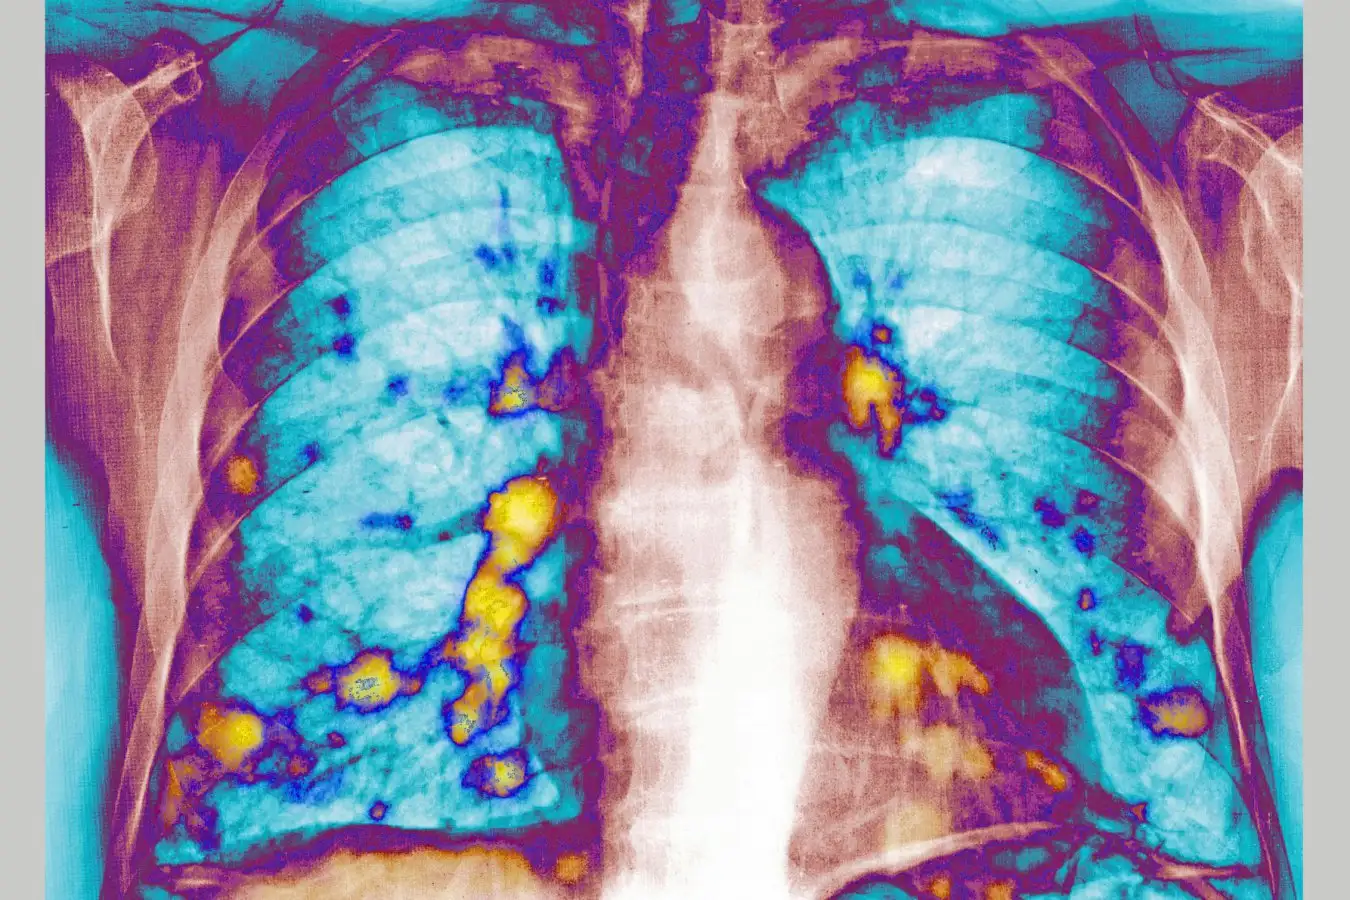

The lungs are one of the most common places for cancers to spread to from elsewhere in the body

The lungs are one of the most common sites for cancer to spread to, which has made the role of respiratory infections like flu, covid-19 and cold-causing viruses an area of considerable interest to scientists.